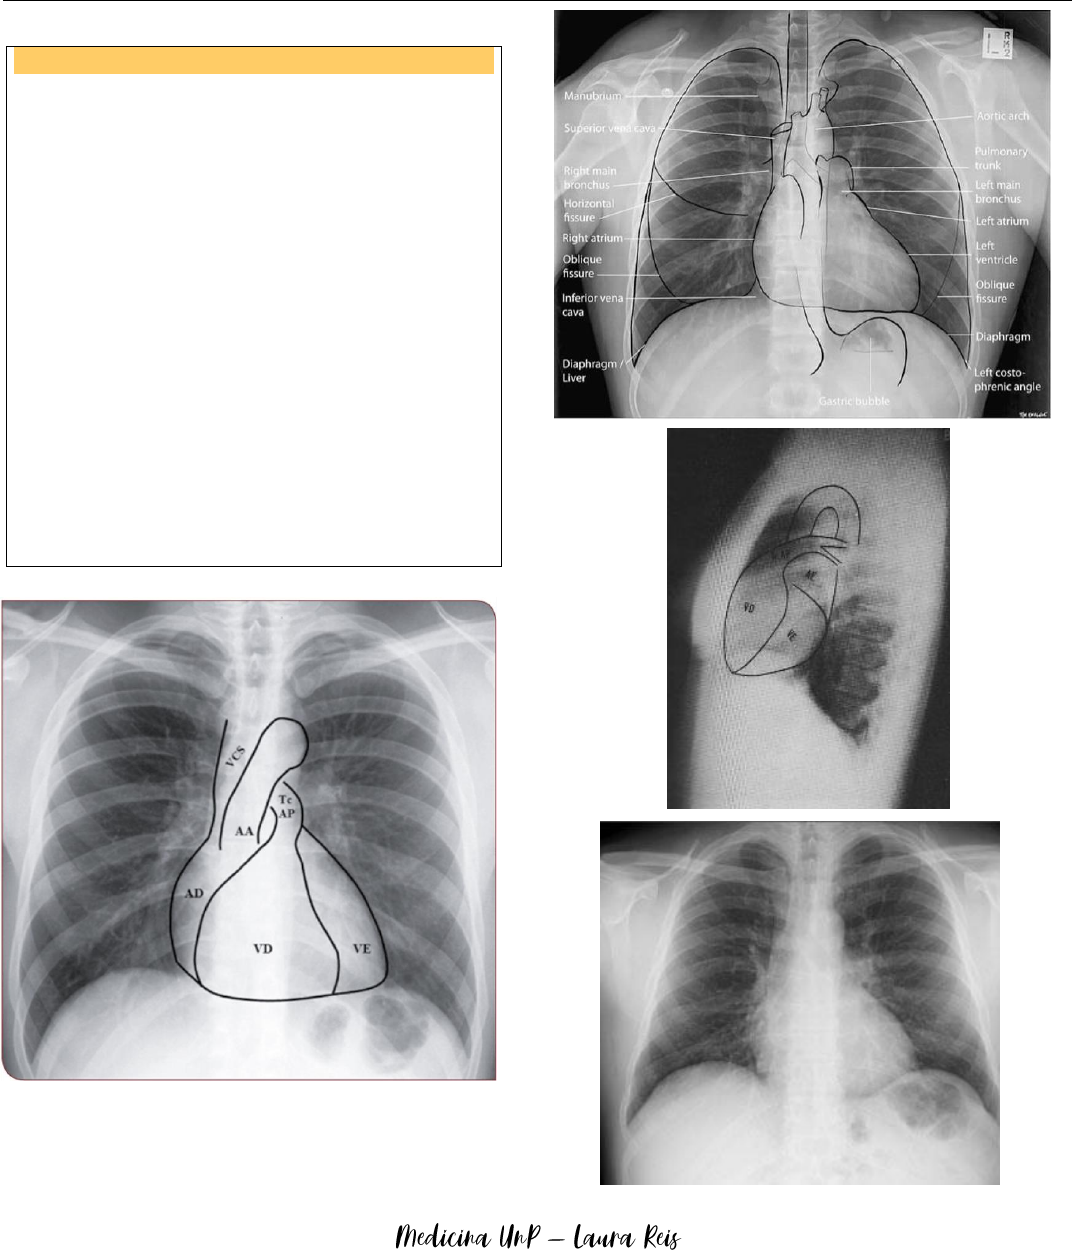

Raio X de torax

Fonte: Aula do Prof. Thiago Dantas

INCIDÊNCIAS

 Postero anterior: melhor para ver pulmão.

− Posição ortostática, raio incidindo pelas

costas, em inspiração, clavícula alinhadas e

traqueia centralizada, visualização dos seios

costofrênicos.

− Diafragma direito mais elevado que o

esquerdo (fígado), presença de bulha gástrica

no diafragma esquerdo, até 8 arcos costais e

até 7 arcos costais em mulheres → ausência

de hiperinsuflação.

 Antero posterior: pode dar falso diagnóstico de

hiperinsuflação pulmonar.

 Perfil: para ver lobos inferiores, que no PA é

sobreposto pelos outros.

 Decúbito lateral (Laurell): melhor para ver

derrame pleural.

 Oblíquoa e Ápico-lordótica: não são mais

utilizadas, devido ao uso de TC.